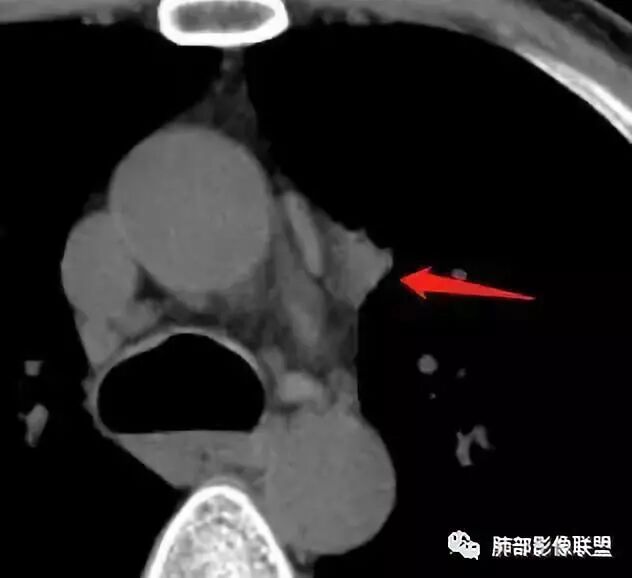

2019.08.24:胸部CT增强扫描:左肺上叶纵膈旁软组织结节影,双肺弥漫性小结节及细网状影,纵膈淋巴结肿大,心包积液,肝左叶散在低密度影。(没见片子)

2019年9月12日CT(外院片,手机拍摄)

现病史:患者于2个月前无明显诱因出现咳痰、咳痰,咳白粘痰或黄痰,有时痰中带血,伴发热,最高体温40.5度,多于下午起热,伴乏力盗汗,有时恶心呕吐,先后至日照市中心医院及青岛大学附属医院住院治疗,给予哌拉西林钠他唑巴坦及拜复乐抗炎,氟康唑抗真菌及对症支持治疗,患者入院检查痰培养(2019-09-08青岛大学附属医院)肺炎克雷伯菌。骨髓穿刺(2019-09-10青岛大学附属医院)检出1.5%异常浆细胞,胞浆kappa单克隆阳性。胸部CT(2019-08-24青岛大学附属医院)左肺上叶软组织影,双肺弥漫小结节并细网状影,纵膈淋巴结肿大,心包积液。自发病来,饮食睡眠差,体重较前下降约15斤。